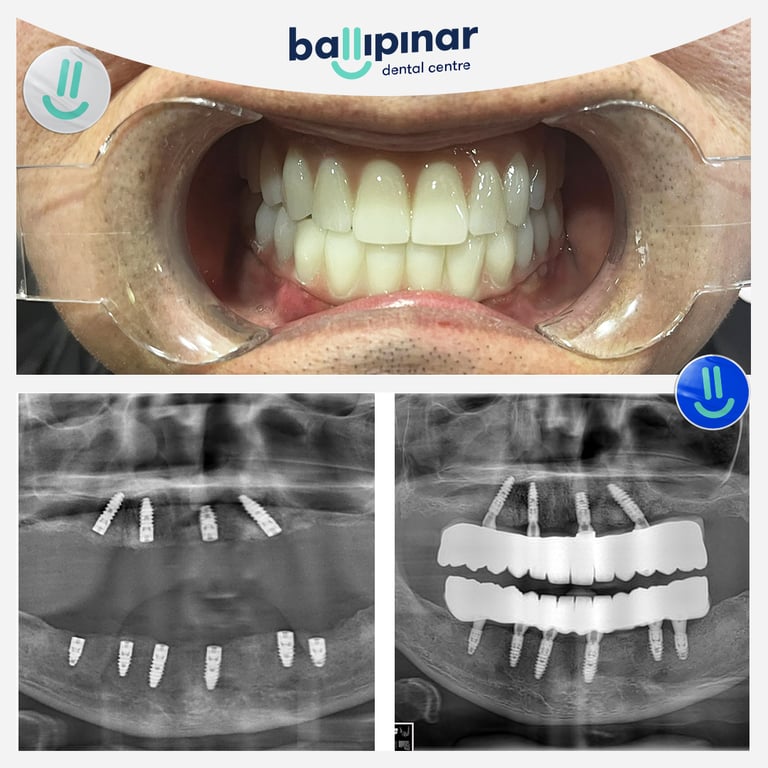

Dental implants Before & After

Explore all the before and after photos of dental implant procedures performed by Ballipinar in Turkey. Contact us today to achieve a beautiful smile.